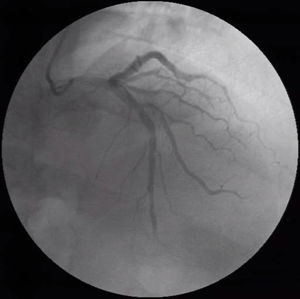

The following year, he developed NYHA class II to III congestive heart failure (HF), requiring uptitration of diuretics. The repeat echocardiogram showed moderate concentric left ventricular hypertrophy, with preserved ejection fraction but an abnormal global longitudinal strain and elevated filling pressures (Figure 3). He repeated the coronary angiography which excluded CAD progression. He underwent a 99mTc-DPD scintigraphy that revealed significant myocardial tracer uptake, diagnosing TTR amyloid infiltration (Figure 4). He was stabilized with medical therapy and kept under close follow-up, requiring antianginal therapy uptitration for exertional microvascular angina.